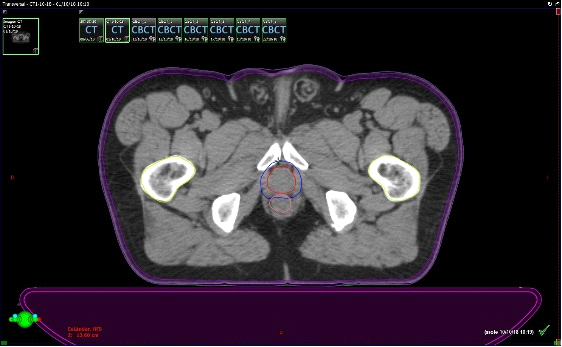

Fig. 3. Técnica de Radioterapia IGRT (Guiada por imágenes). Derecha: TAC de simulación con contornos: Rojo CTV: clinic target volume(próstata y vesículas seminales); Azul: PTV: patologic target volume); Amarillo: Vejiga (OAR); Rosado: Recto (OAR); Verde: Cadera derecha (OAR); Celeste: Cadera izquierda (OAR). Izquierda: Conbeam en máquina de tratamiento, en donde la imagen en el aceleradorse superpone con los contornos hecho en el TAC de simulación.